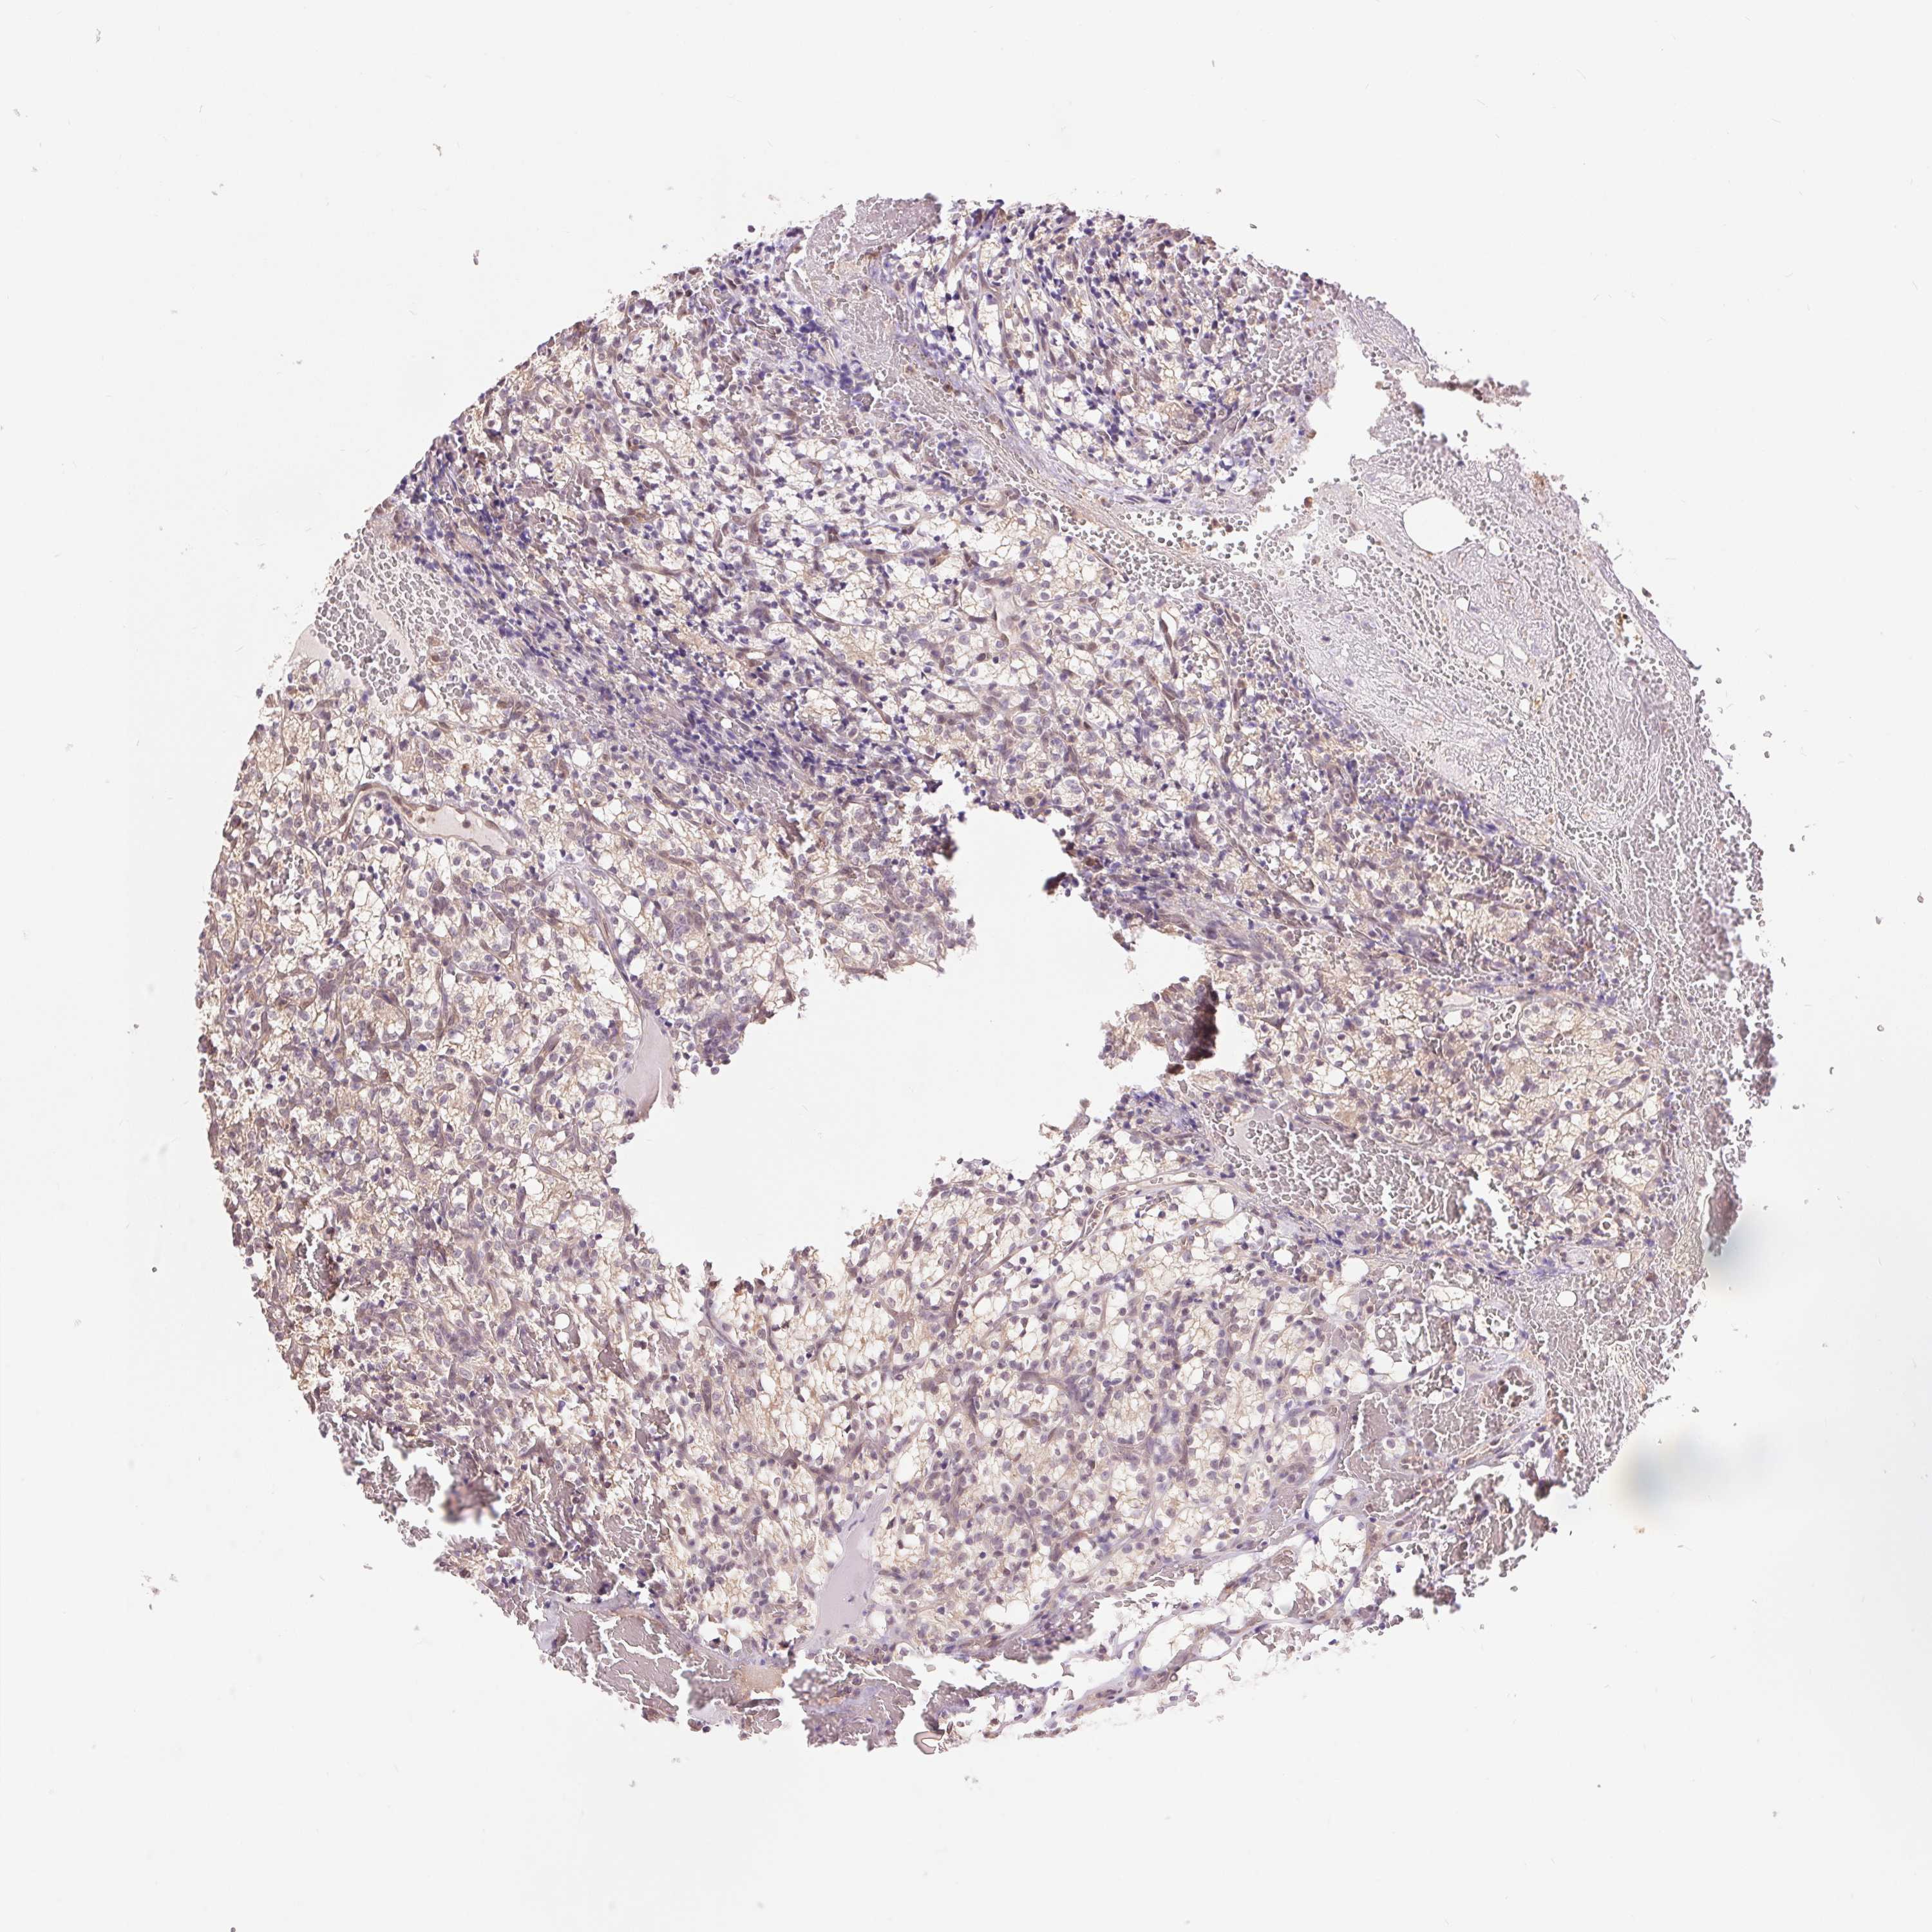

KIDNEY RENAL CLEAR CELL CARCINOMA (VALIDATION) - Interactive survival scatter ploti

The Survival Scatter plot shows the clinical status (i.e. dead or alive) for all individuals in the patient cohort, based on the same data that underlies the corresponding Kaplan-Meier plots. Patients that are alive at last time for follow-up are shown in blue and patients who have died during the study are shown in red.

The x-axis shows the expression levels (FPKM) of the investigated gene in the tumor tissue at the time of diagnosis. The y-axis shows the follow-up time after diagnosis (years). Both axes are complimented with kernel density curves demonstrating the data density over the axes. The top density plot shows the expression levels (FPKM) distribution among dead (red) and alive patients (blue). The right density plot shows the data density of the survived years of dead patients with high and low expression levels respectively, stratified using the cutoff indicated by the vertical dashed line through the Survival Scatter plot. This cutoff is automatically defined based on the FPKM cutoff that minimizes the p-score. The cutoff can be changed by dragging the vertical line or by entering a cutoff value in the square labeled "Current cut-off".

Under the Survival Scatter plot the p-score landscape (black curve; left axis) is shown together with dead median separation (red curve; right axis). Dead median separation is the difference in median mRNA expression between patients who have died with high and low expression, respectively. It is calculated as follows: median FPKM expression of dead patients with high expression - median FPKM expression of dead patients with low expression. This is intended to aid the user in visually exploring custom cutoffs and the associated p-scores and dead median separation.

Individual patient data is displayed and can be filtered by clicking on one or more of the category buttons on the top of the page. Categories describing expression level and patient information include: high, low, alive, dead, female, male and tumor stages. The scale of the x-axis can be toggled between linear and log-scale by clicking on the "x log" button. Mouse-over function shows TCGA ID, patient information and mRNA expression (FPKM) for each patient.

& Survival analysisi

Kaplan-Meier plots summarize results from analysis of correlation between mRNA expression level and patient survival. Patients were divided based on level of expression into one of the two groups "low" (under cut off) or "high" (over cut off). X-axis shows time for survival (years) and y-axis shows the probability of survival, where 1.0 corresponds to 100 percent.

TMEM273 is not prognostic in Kidney Renal Clear Cell Carcinoma (validation)

Best expression cut offi

Based on the FPKM value of each gene, patients were classified into two groups and association between prognosis (survival) and gene expression (FPKM) was examined. The best expression cut-off refers the FPKM value that yields maximal difference with regard to survival between the two groups at the lowest log-rank P-value. Best expression cut-off was selected based on survival analysis .

When clicking on this number, the vertical dashed line indicating cut-off, the interactive survival plot, and the Kaplan-Meier curve will be adjusted to show results based on the best expression cut-off.

: 7.69

P scorei

Log-rank P value for Kaplan-Meier plot showing results from analysis of correlation between mRNA expression level and patient survival.

N/A

TCGA RNA samplesi

RNA-seq data is reported as average FPKM (number Fragments Per Kilobase of exon per Million reads), generated by the The Cancer Genome Atlas (TCGA) .

Normal distribution across the dataset is visualized with box plots, shown as median and 25th and 75th percentiles. Points are displayed as outliers if they are above or below 1.5 times the interquartile range. FPKM values of the individual samples are presented next to the box plot.

Average pTPM 17.3

Number of samples 100